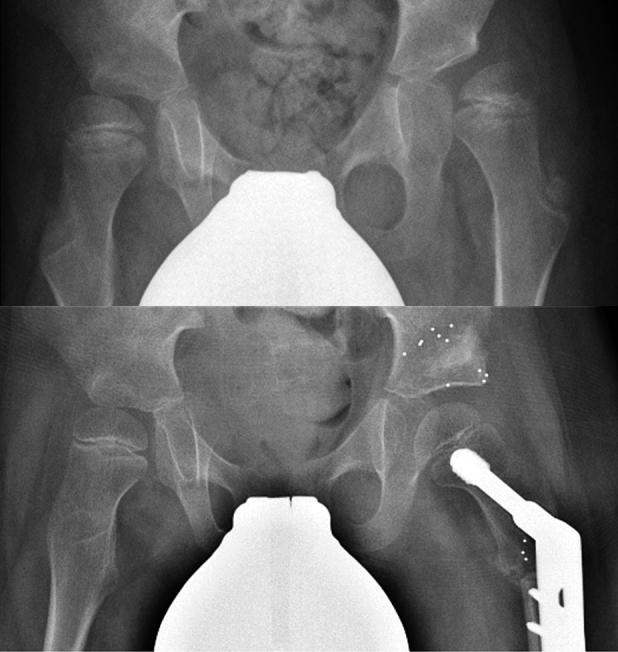

Background and purpose - Studies have indicated that one-third of children with cerebral palsy (CP) develop dislocation of the hip that needs surgical intervention. When hip dislocation occurs during childhood surgical treatment consists of tenotomies, femoral varus derotation osteotomy (VDRO), and acetabuloplasty. Relapse is observed in one-fifth of cases during adolescence. In this prospective cohort study, we performed a descriptive evaluation of translation and rotation across VDROs in children with neuromuscular disorders and syndromes by radiostereometric analysis (RSA). We assessed "RSA stability" and migration across the VDROs. Patients and methods - Children with a neuromuscular disorder were set up for skeletal corrective surgery of the hip. RSA follow-ups were performed postoperatively, at 5 weeks, and 3, 6, and 12 months after surgery. Results - 27 femoral VDROs were included; 2 patients were excluded during the study period. RSA data showed stability across the VDRO in the majority of cases within the first 5 weeks. At the 1-year follow-up, the mean translations (SD) of the femoral shaft distal to the VDRO were 0.51 (1.12) mm medial, 0.69 (1.61) mm superior, and 0.21 (1.28) mm posterior. The mean rotations were 0.39° (2.90) anterior tilt, 0.02° (3.07) internal rotation, and 2.17° (2.29) varus angulation. Interpretation - The migration stagnates within the first 5 weeks, indicating stability across the VDRO in most patients.

背景与目的——研究表明,三分之一的脑瘫患儿会发生髋关节脱位,需要手术干预。儿童期发生髋关节脱位时,手术治疗包括肌腱切断术、股骨内翻旋转截骨术(VDRO)和髋臼成形术。青春期有五分之一的病例会出现复发。在这项前瞻性队列研究中,我们通过放射立体测量分析(RSA)对神经肌肉疾病和综合征患儿的VDRO手术中的平移和旋转进行了描述性评估。我们评估了VDRO手术中的“RSA稳定性”和移位情况。

患者与方法——患有神经肌肉疾病的儿童准备接受髋关节骨骼矫正手术。术后、术后5周以及术后3、6和12个月进行RSA随访。

结果——纳入27例股骨VDRO手术;研究期间排除2例患者。RSA数据显示,在最初5周内,大多数病例的VDRO手术具有稳定性。在1年随访时,VDRO远端股骨干的平均平移(标准差)为内侧0.51(1.12)mm、上方0.69(1.61)mm和后方0.21(1.28)mm。平均旋转角度为前倾0.39°(2.90)、内旋0.02°(3.07)和内翻成角2.17°(2.29)。

解读——移位在最初5周内停滞,表明大多数患者的VDRO手术具有稳定性。